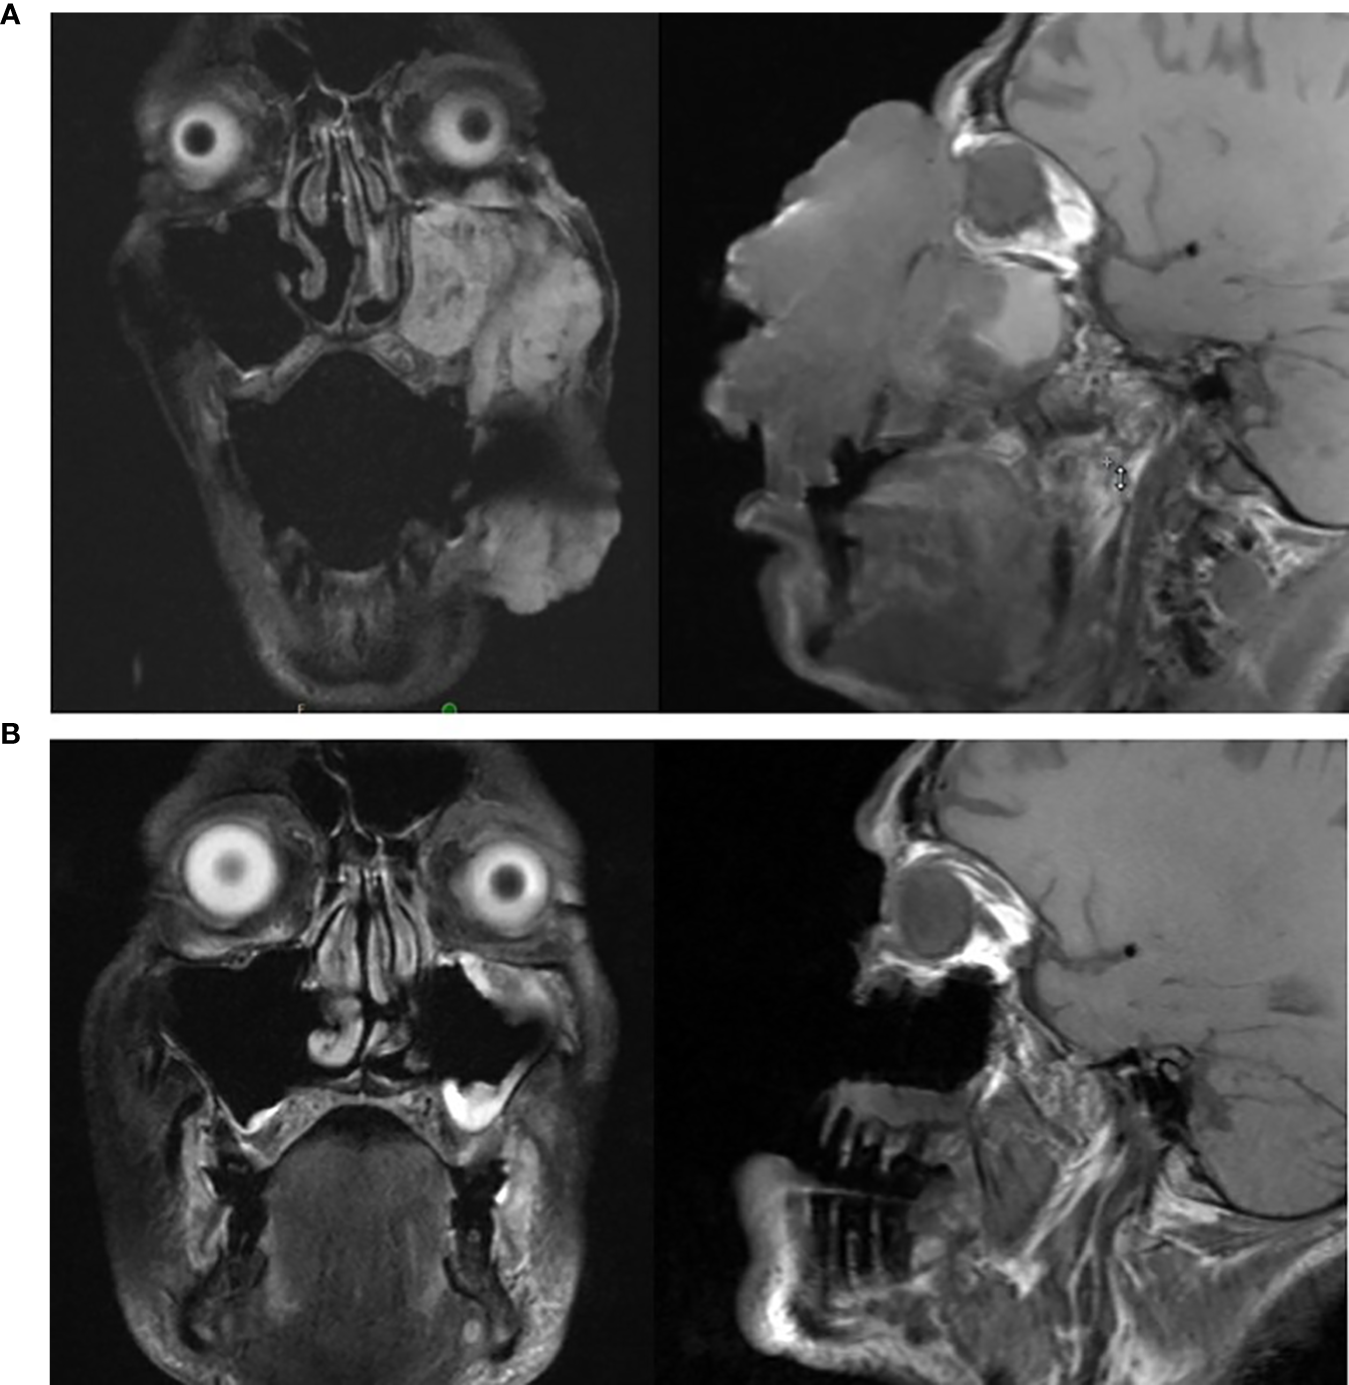

Figure 3

(A, B): (A) (top): MRI of head prior to initiating cemiplimab; (B) (bottom): MRI of head following completion of cemiplimab.

Cemiplimab was initiated on November 8, 2020. On November 23, 2020, the patient presented to the emergency department (ED) with an increase in the size of his facial mass and bleeding. This was assumed to be a flare (pseudoprogression) after immunotherapy. Radiation oncology recommended QUAD shot radiotherapy (RT) with 14 Gy, delivered in 4 fractions (twice per day for 2 days) every 3 weeks for 4 cycles. The lesion shrunk between the CT simulation and the radiation initiation and became drier. Cycle 1, day 1 QUAD shot was completed on November 30, 2020 (Figure 2C). Cycle 2 Day 2 cemiplimab was given on December 3, 2020. Following the second dose of cemiplimab + first radiation cycle, the lesion decreased by 75% with significant improvement from disease involvement near the eye. Cycle 2, day 1 QUAD shot was given on December 17, 2020 (Figure 2D), and cycle 3, day 1 cemiplimab was given on December 23, 2020. There was a further 75% reduction in the size of the mass (Figure 2E), but the patient developed grade-2 hypothyroidism. Radiation was then held after 50% of the dose was delivered. Following cycle 4 of cemiplimab, with cycle 4, day 1 on January 4, 2021, the patient developed two fistulas in his maxillary sinus and nasal cavity, which were determined to be sites of disease regression (Figure 2F). A facial MRI from January 27, 2021 revealed near-complete regression of the tumor in the inferior orbit (Figure 3B), indicating the patient may be able to avoid left orbital exenteration, which would have been indicated prior to ICI treatment. Cemiplimab was held on February 4, 2021 prior to cycle 5 of cemiplimab due to grade-1 transaminitis. The patient’s AST and ALT levels improved after treatment was held. Four biopsies were taken across the lesion on February 4, 2021, revealing no evidence of residual cancer. As his disease had significantly regressed, the care team felt that the patient had reached the point of maximal response. To salvage as much viable tissue as possible, the patient was referred to surgery for debridement of necrotic tissue and reconstruction (Figure 2G).